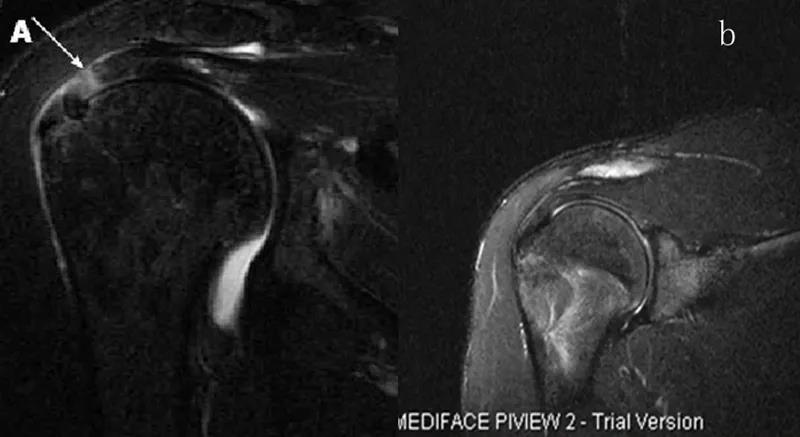

图22 斜矢状位 a.冈上肌出口,肩袖诊断不如斜冠状位;b.冈上肌及肌腹脂肪浸润成度,评估手术与否